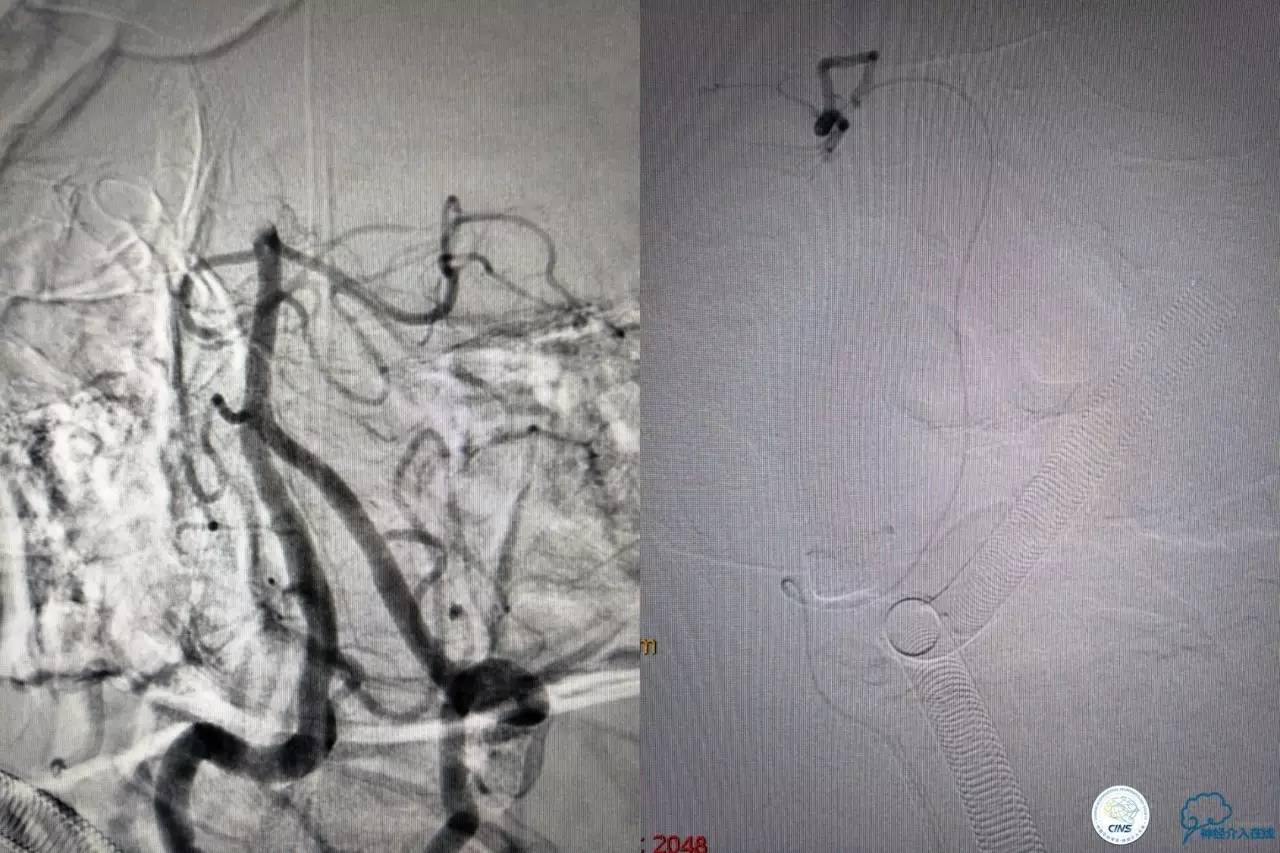

好大的血栓,支架释放后,血管无复流,拉一把!

没错,没看错!血管成功实现再通,术中取栓的栓子如下。

术后

术后生命体征平稳,成功撤呼吸机,肌力较前好转,复查头颅CT:

右侧丘脑高密度影,右侧枕叶可能也有梗死,祈祷慢慢恢复吧!